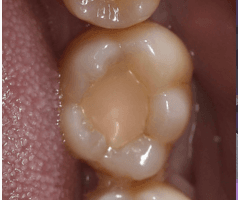

After Photo

Dr Deesha